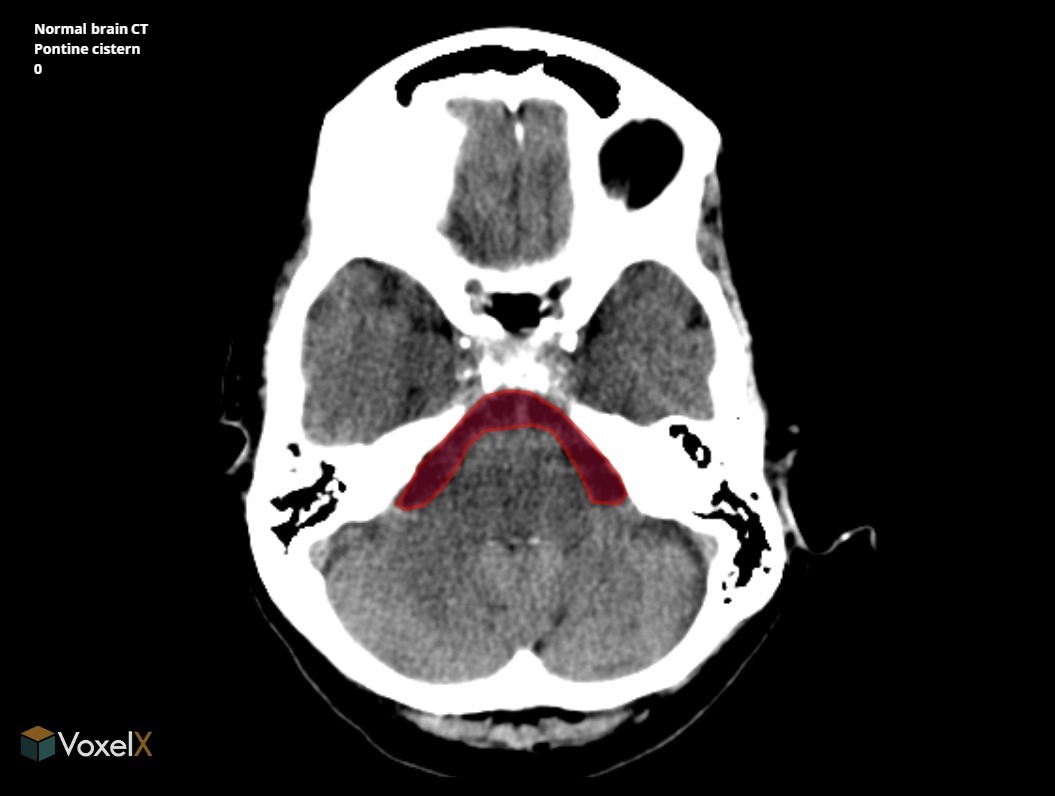

What is the name of the dilatated subarachnoid space into which foramen luschke open?

A

(Cerebello)Pontine cistern

S2